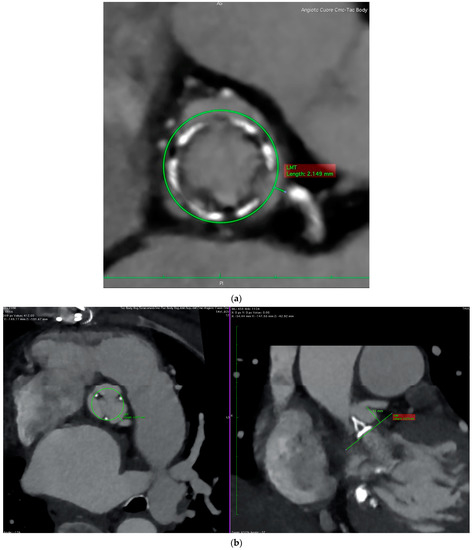

- Dvir, D.; Leipsic, J.; Blanke, P.; Ribeiro, H.B.; Kornowski, R.; Pichard, A.; Rodés-Cabau, J.; Wood, D.A.; Stub, D.; Ben-Dor, I.; et al. Coronary obstruction in transcatheter aortic valve-in-valve implantation: Preprocedural evaluation, device selection, protection, and treatment. Circ. Cardiovasc. Interv. 2015, 8, e002079. [Google Scholar] [CrossRef]

- Ochiai, T.; Oakley, L.; Sekhon, N.; Komatsu, I.; Flint, N.; Kaewkes, D.; Yoon, S.-H.; Raschpichler, M.; Patel, V.; Tiwana, R.; et al. Risk of Coronary Obstruction Due to Sinus Sequestration in Redo Transcatheter Aortic Valve Replacement. JACC Cardiovasc. Interv. 2020, 13, 2617–2627. [Google Scholar] [CrossRef]

- Tang, G.H.; Komatsu, I.; Tzemach, L.; Simonato, M.; Wolak, A.; Blanke, P.; Dvir, D. Risk of coronary obstruction and the need to perform BASILICA: The VIVID classification. EuroIntervention 2020, 16, e757–e759. [Google Scholar] [CrossRef]

- Tomii, D.; Okuno, T.; Lanz, J.; Stortecky, S.; Reineke, D.; Windecker, S.; Pilgrim, T. Valve-in-valve TAVI and risk of coronary obstruction: Validation of the VIVID classification. J. Cardiovasc. Comput. Tomogr. 2023; in press. [Google Scholar] [CrossRef]